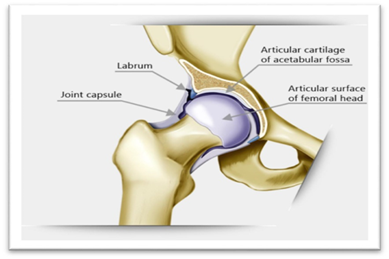

The hip may be a genuine ball and attachment joint as shown in Figure 1. This course of action gives the hip the expansive sum of movement required for everyday exercises like strolling, hunching down, and stair climbing. How the distinctive layers of the hip are orchestrated and associated can assist to get how the hip works, how it can be harmed, and how challenging recuperation can be when this joint is harmed or harmed by joint pain. The most profound layer of the hip incorporates the bones and the joints. The other layer is made up of the tendons of the joint capsule and at long last, these tendons are secured by the imperative ligaments and the muscles that offer assistance to move the leg. The imperative structures of the hip can be partitioned into a few categories: these incorporate bones and joints, tendons and ligaments, muscles, nerves, blood vessels, and Bursae. Articular cartilage is the fabric that covers the closes of the bones of any joint. It is almost around 1/4 inch thick within the large weight-bearing joints like the hip. It looks like a white and glossy thing and encompasses a rubbery consistency. It is elusive which permits the joint administrations to slide against one another without causing any harm. The work of articular cartilage is to assimilate stun and give a greatly smooth surface to create movement simpler. This is very much asymmetric with the tribological behavior of mechanical engineering.

Figure 1 Hip joint and cartilage.13